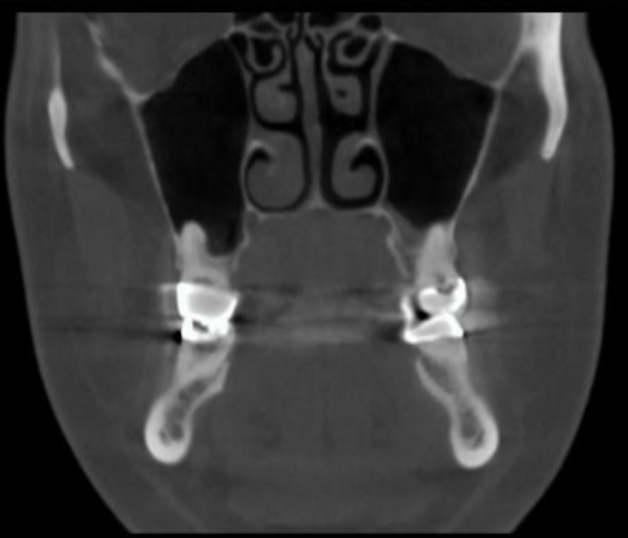

coronal

what plane is this slice